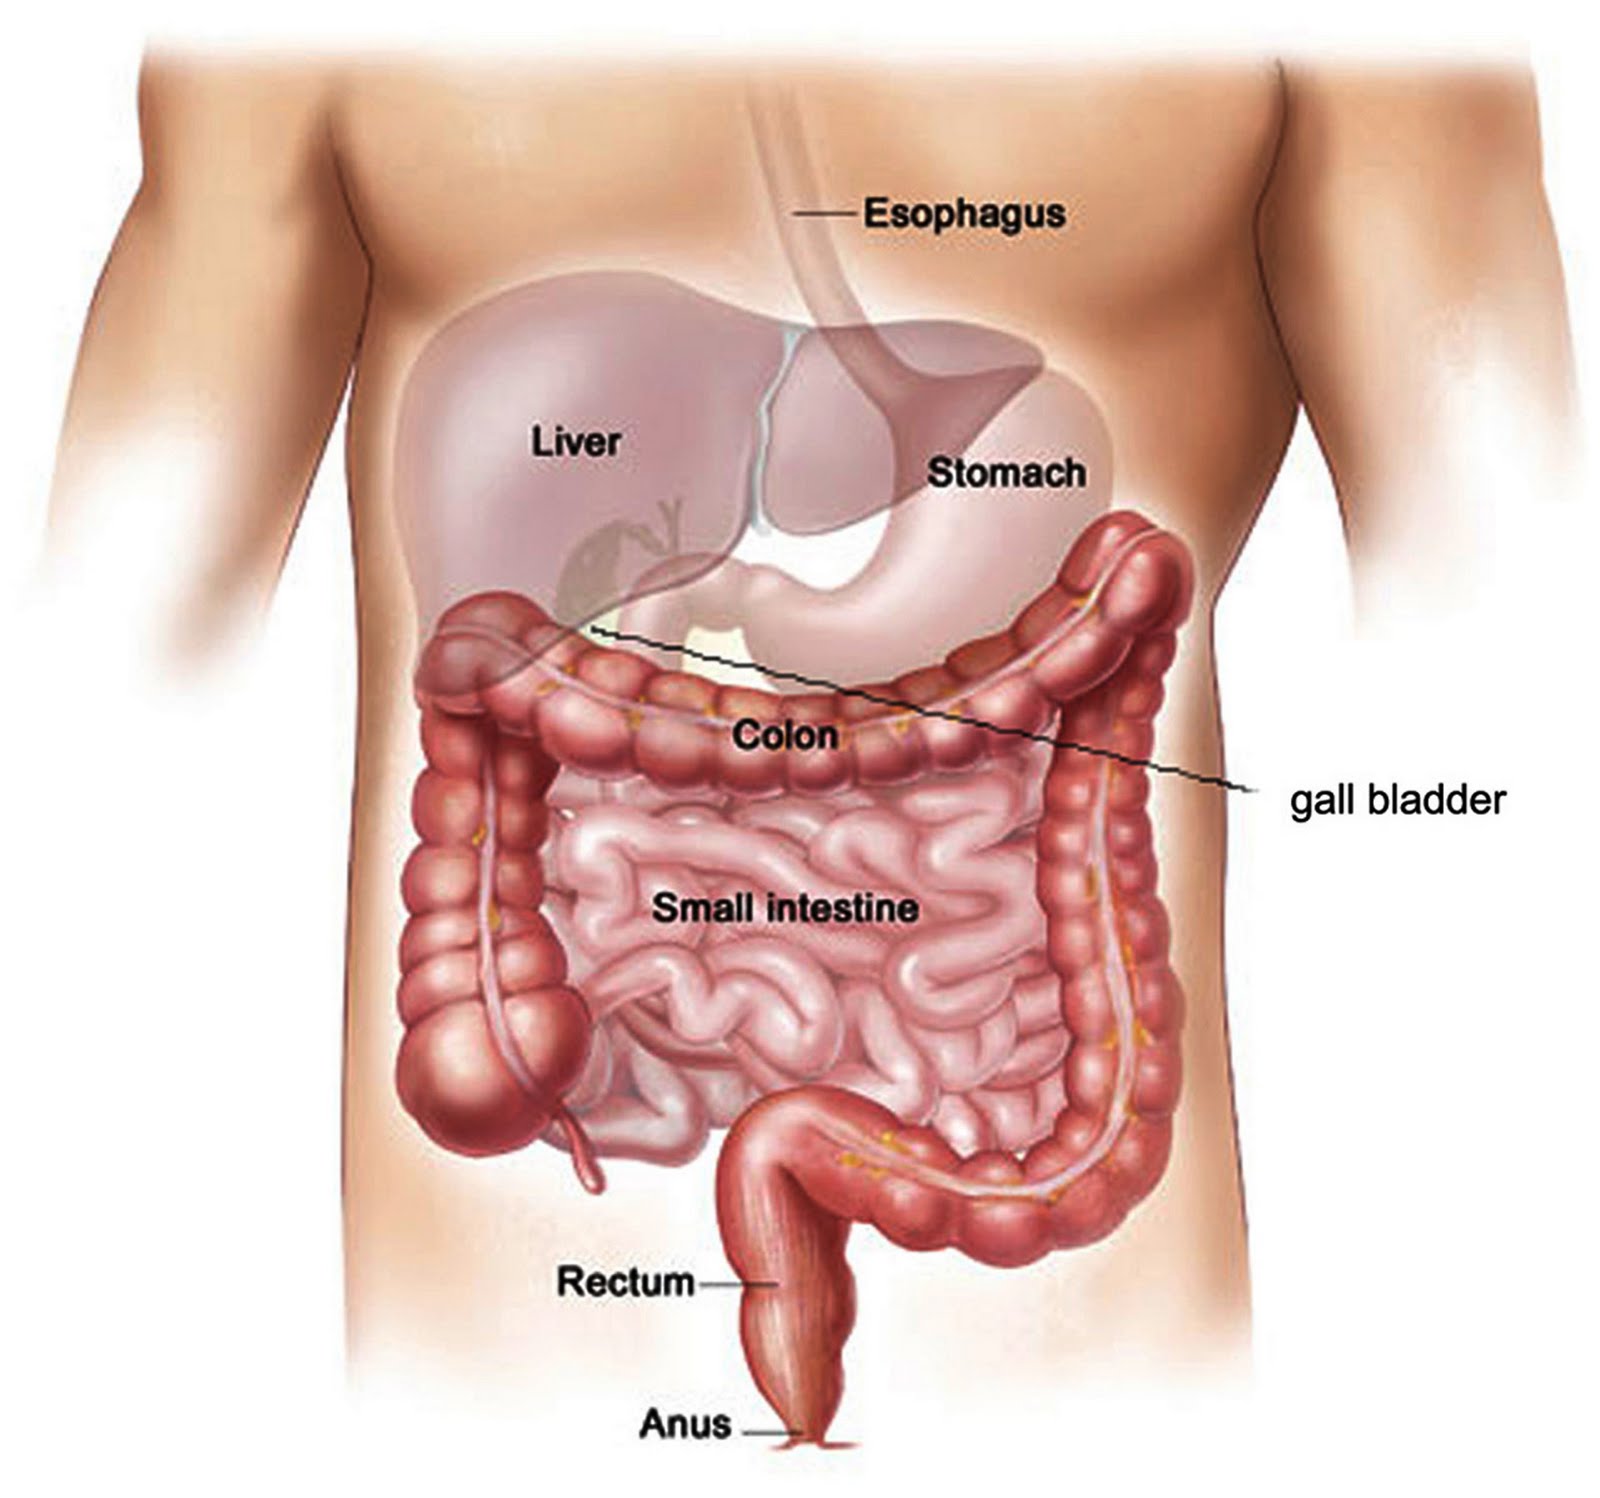

Ask the (Science-Based) Pharmacist: What are the benefits of coffee enemas?

It might not occur to you, sipping your morning coffee, that you could derive tremendous health benefits by simply shooting that coffee directly into your rectum. Yet many people believe this. Suzy Cohen, who calls herself, “America’s Pharmacist™” and also “America’s Most Trusted Pharmacist®” is a proponent. Her syndicated column Ask the Pharmacist recently contained this question and response:

Naturopathic organ repositioning coming soon to Pennsylvania?